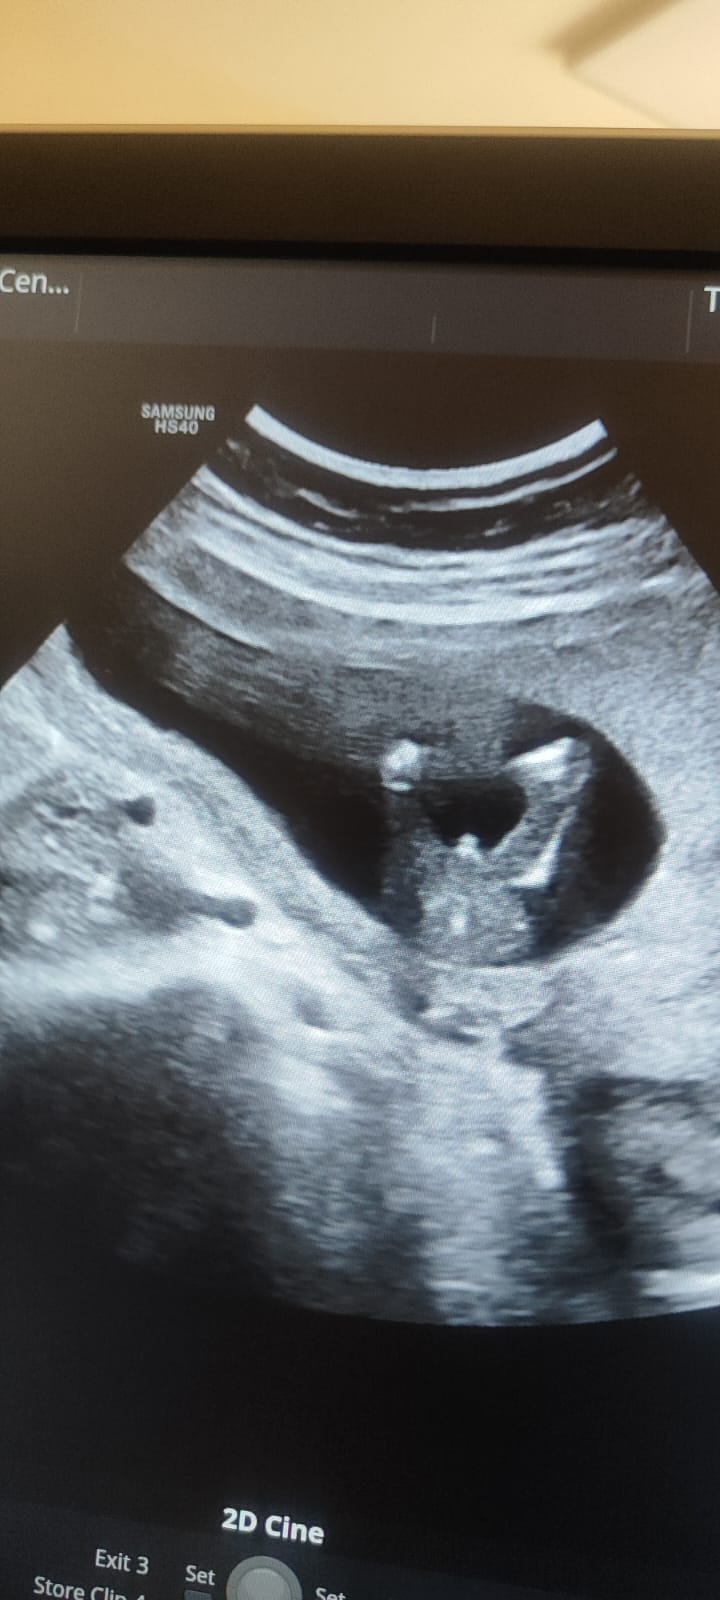

تحديد جنس الجنين في الاسبوع ١٥ من الحمل

اريد تحديد جنس الجنين الاسبوع ١٥ مرفقا صورة

غالبا ذكر.... 0 2026-03-18T22:06:10+00:00 2026-03-18T22:06:10+00:00

غالبا ذكر....